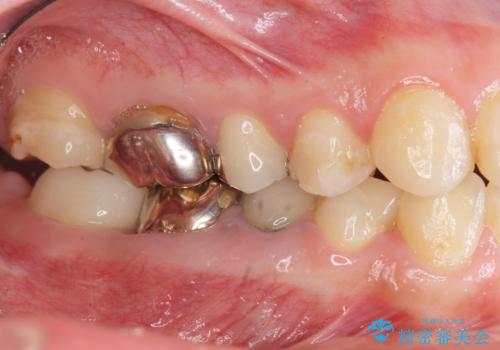

- 20代女性

- 「地元の歯医者にずっと通っているが、どんどん歯が悪くなる。時間とお金がかかってもいいので徹底的に歯を治したい。」

、と総合的な歯科治療を希望されて来院されました。

虫歯や咬合関係・歯槽骨の吸収・根尖病変・歯の欠損・複合的な問題を一つずつ解決し、

安定した噛み合わせの構築・歯ブラシのしやすい環境の整備・歯内歯周の感染除去・造骨を伴うインプラント治療

を行い、長期的な予後を見込める口腔内環境を確立、整備して行きます。